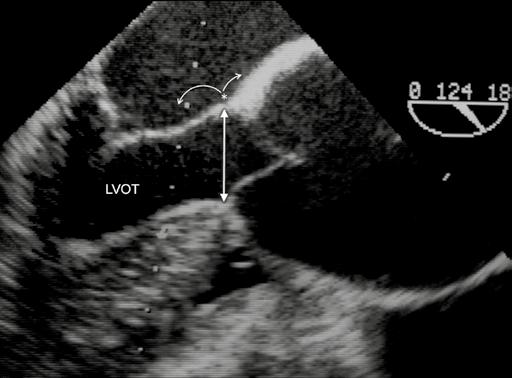

Různé diagnostické postupy a techniky si všímají bazálního prstence (BR), aortálních sinusů, sinotubulární junkce (STJ), vzestupné aorty a výtokového traktu levé komory (LVOT) (obr. 1-10). Jak již bylo uvedeno [4], bazální prstenec představuje myšlený kruh, který spojuje nejnižší body listů aortální chlopně [14]. V případě aortální nedomykavosti je bazální prstenec dislokován do výtokového traktu levé komory, naopak u aortální stenózy a retrakce listů se bazální prstenec posouvá do aorty. V některých případech je obtížné či téměř nemožné bazální prstenec definovat (obr. 1-11). Někteří autoři dávají přednost nejdistálnější části výtokového traktu levé komory na úrovni aortomitrálního ohybu. Ani tento bod není fixní – bod závěsu se posouvá směrem k volnému okraji předního listu mitrální chlopně v případě mitrální nedomykavosti [15] (obr. 1-12). Pravděpodobně nejspolehlivější a nejpřesnější je přímé měření Hegarovým dilatátorem v průběhu operace. U bikuspidální aortální chlopně je měření BR spojeno s dalšími specifickými obtížemi. Správné stanovení rozměrů BR je u záchovných výkonů na aortálním kořeni důležité vzhledem k tomu, že je zapotřebí stabilizovat nebo upravit správný poměr mezi BR a STJ [16]. Hodnocení aortálního kořene na úrovni sinusů rovněž vyžaduje obezřetnost. Obvyklé zobrazení představuje hruškovitě tvarovaný kořen se dvěma protilehlými sinusy. Tento průměr sinus-sinus ve skutečnosti nepředstavuje skutečný průřez středem aortálního kořene. Řez dělící kořen na dvě poloviny zobrazuje ve skutečnosti vzdálenost mezi sinusem a protilehlou komisurou (obr. 1-13). Navíc vzhledem k normální asymetrii aortálního kořene je nutno vzít v potaz řadu podobných dalších průměrů. Záchovné výkony na aortálním kořeni vyžadují přesnou kalibraci. Průměr STJ a výška listů aortální chlopně (2/3 výšky) spolu s výškou komisur představují základní chirurgické parametry. Chlopenní listy jsou zejména u aneurysmat aortálního kořene asymetrické a větší než normálně [17]. Měření všech rozměrů musí být doprovázena klinickým úsudkem.

Obr. 1-10 Průměry a měření při kalibraci aortálního kořene. Při diagnostickém zobrazení i intraoperačním hodnocení jsou potřebné přesné orientační body a měření. Jsou stanoveny následující parametry: bazální prstenec (BR), průměr v úrovni sinusů (Sin), sinotubulární junkce (STJ) a vzestupná aorta (AA). Nezřídka – i během operace – je důležitý rozměr výtokového traktu levé komory (LVOT) mezi komorovou přepážkou a předním listem mitrální chlopně (AML).

Obr. 1-12 Průměr výtokového traktu levé komory. Vzdálenost mezi komorovou přepážkou a aortomitrálním přechodem představuje správné měření LVOT. Nicméně nejvíce prominující oblast septa nebývá v úrovni úponů aortální chlopně, ale níže ve výtokovém traktu levé komory, jak tomu je zejména u hypertrofické kardiomyopatie. Naopak aortomitrální přechod může být dislokován, a to směrem k volnému okraji předního cípu mitrální chlopně u mitrální regurgitace nebo směrem dovnitř aorty u aortální a/nebo mitrální stenózy. Během operace se průměr LVOT měří nejsnáze Hegarovým dilatátorem.